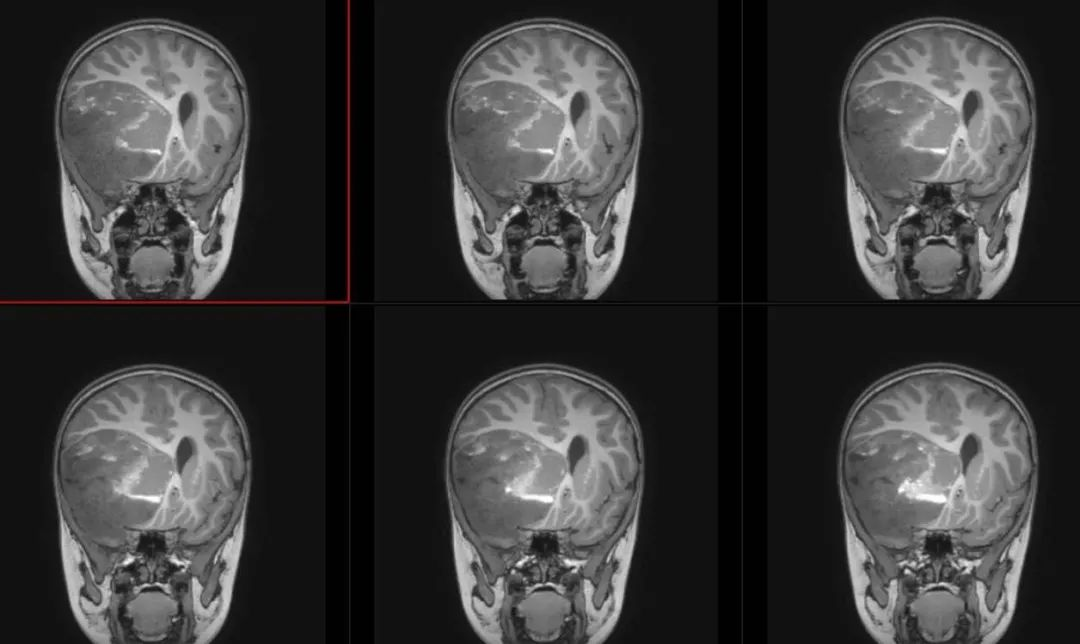

术前T1冠状位